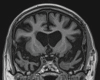

Neurodegenerative diseases are a devastating group of disorders that can be difficult to accurately diagnose. Although these disorders are difficult to manage owing to relatively limited treatment options, an early and correct diagnosis can help with managing symptoms and coping with the later stages of these disease processes. Both anatomic structural imaging and physiologic molecular imaging have evolved to a state in which these neurodegenerative processes can be identified relatively early with high accuracy. To determine the underlying disease, the radiologist should understand the different distributions and pathophysiologic processes involved. High-spatial-resolution MRI allows detection of subtle morphologic changes, as well as potential complications and alternate diagnoses, while molecular imaging allows visualization of altered function or abnormal increased or decreased concentration of disease-specific markers. These methodologies are complementary. Appropriate workup and interpretation of diagnostic studies require an integrated, multimodality, multidisciplinary approach. This article reviews the protocols and findings at MRI and nuclear medicine imaging, including with the use of flurodeoxyglucose, amyloid tracers, and dopaminergic transporter imaging (ioflupane). The pathophysiology of some of the major neurodegenerative processes and their clinical presentations are also reviewed; this information is critical to understand how these imaging modalities work, and it aids in the integration of clinical data to help synthesize a final diagnosis. Radiologists and nuclear medicine physicians aiming to include the evaluation of neurodegenerative diseases in their practice should be aware of and familiar with the multiple imaging modalities available and how using these modalities is essential in the multidisciplinary management of patients with neurodegenerative diseases.©RSNA, 2020.